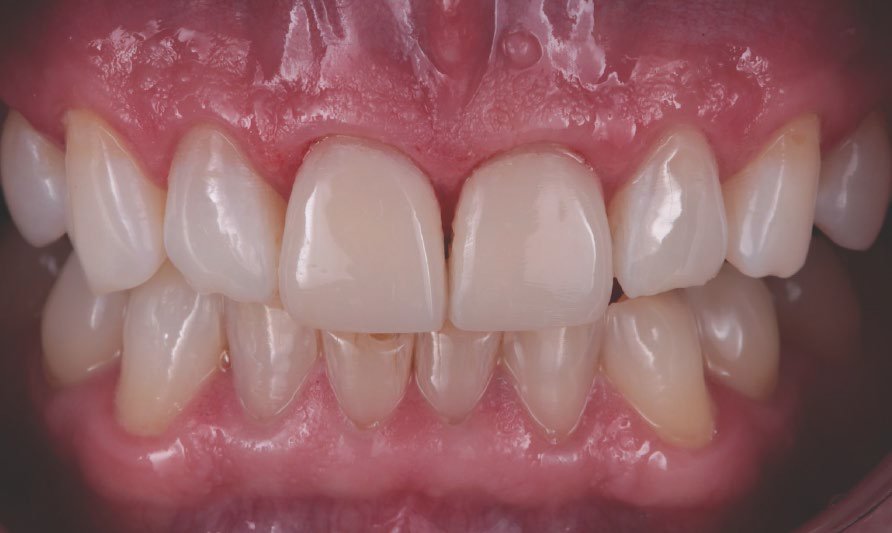

Final result

Treatment outcome immediately after rubber dam removal. The discolorations were gone, the restorations and the adjacent teeth had a similar shade, and a natural shape was achieved.